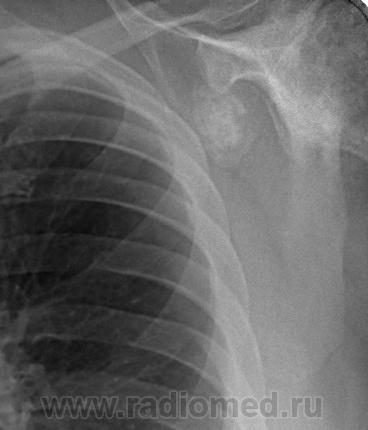

Пациент 60 лет, при прохождении проверочной флюорографии  обнаружены изменения со сторны плечевых суставов.Водитель троллейбуса.Страдает избыточной массой тела, люмбальгией, артороз коленных суставов.Непосредственно жалобы на плечевые суставы в медицинских документах не отражены. Какое будет мнение у коллег?

Пациент жалоб со сторны плечевых суставов не предъяляет и не помнит что бы когда- то что то беспокоило.Данных за сирингомиелию нет.

Александр, конечно надо доснять плечевые суставы... Из того, что есть: видимые отделы плечевых костей выглядят довольно симметрично, хотя слева и похуже, думаю - артроз. Весьма настораживает левая лопатка на предмет хондросаркомы

Снимки плечевых суставов.

Уважаемый Александр, приходиться признать, что на цифровой рентгенограмме легких изменения плечевых суставов видны лучше, чем на "обрезаных" и недоэкспонированых снимках суставов. По имеющимся данным могу только сказать, что деф. артроз с кистовидной перестройкой структуры есть. Под хрящевой опухолью (возможно - хондросаркома) левой лопатки я имела в виду тень, отмеченую красными стрелками, которая в поле снимка не вошла. Моя вина - в силу специфики работы такие узкоформатные снимки давно были вредными, т.к. очень часто патология остается за пределами снимка. Остается рекомендовать рентгенография левой лопатки в прямой передне-задней и косой проекциях, а лучше - КТ...